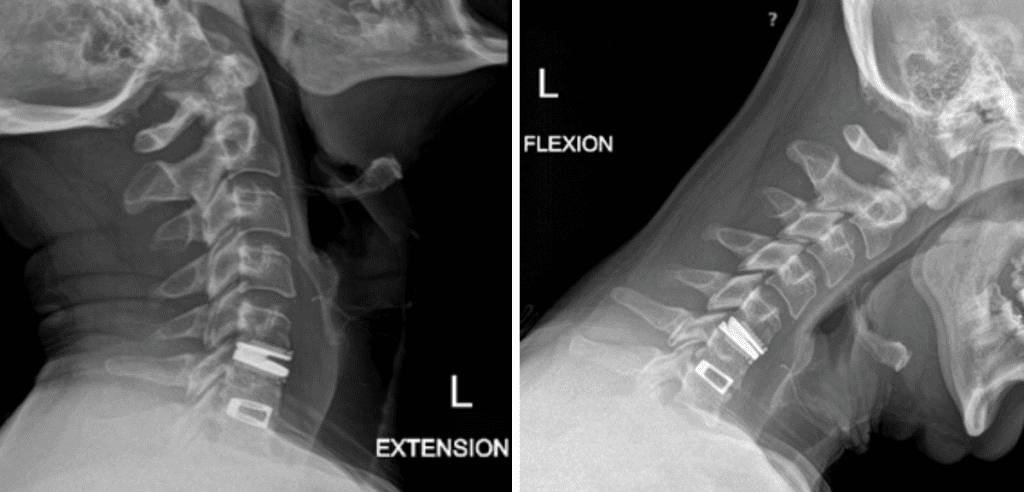

This is a 42-year-old otherwise healthy male who presented electively with progressively worsening neck pain radiating down the left arm, with paresthesia first three digits. He had a previous C6-7 anterior cervical discectomy and fusion (ACDF) two years prior, for which he recovered well. He was referred to Dr. Xavier Gaudin for a neurosurgical spine evaluation. An MRI cervical spine was obtained, which demonstrated C5-6 adjacent segment degenerative disease with a large disc extrusion resulting in severe left lateral recess and foraminal stenosis (Figure 1).

Figure 1: Preoperative MRI demonstrating C5-6 disc herniation with stenosis, adjacent to the previous C6-7 ACDF.